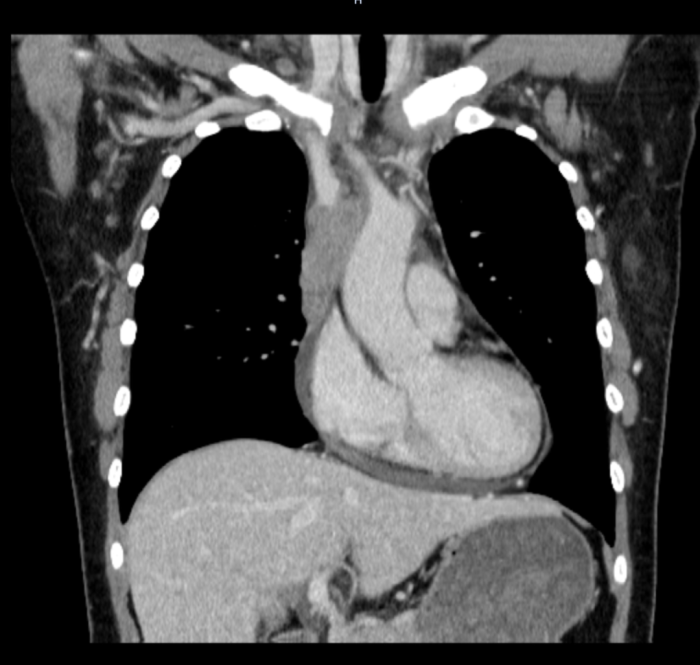

术后CT证实人工血管通畅,患者上半身水肿消失

术中,梁恒星主任仅用时3小时,便完整切除了患者前纵隔肿瘤,同时在非体外循环下进行了上腔静脉切除并完成人工血管置换。此外,梁恒星主任还对患者受累及的左无名静脉和右上肺叶部分组织进行了切除。患者术后也取得了立竿见影的效果——面部浮肿开始消退,双上肢臂围也日渐缩小,头痛欲裂的感觉也消失得无影无踪。最终的病理检查结果也令颜女士和她的家人感到欣慰——胸腺癌病灶被完整切除,所有切缘都没有肿瘤细胞残留。